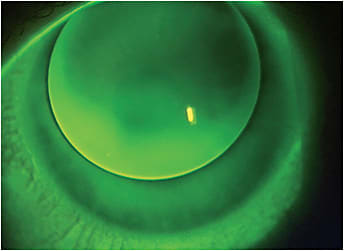

Lid tension is important to note when fitting higher refractive errors. A loose upper lid may push down a thicker minus lens edge, while a tight lid might “grab” a minus edge and cause undesirable superior decentration (Figure 1).